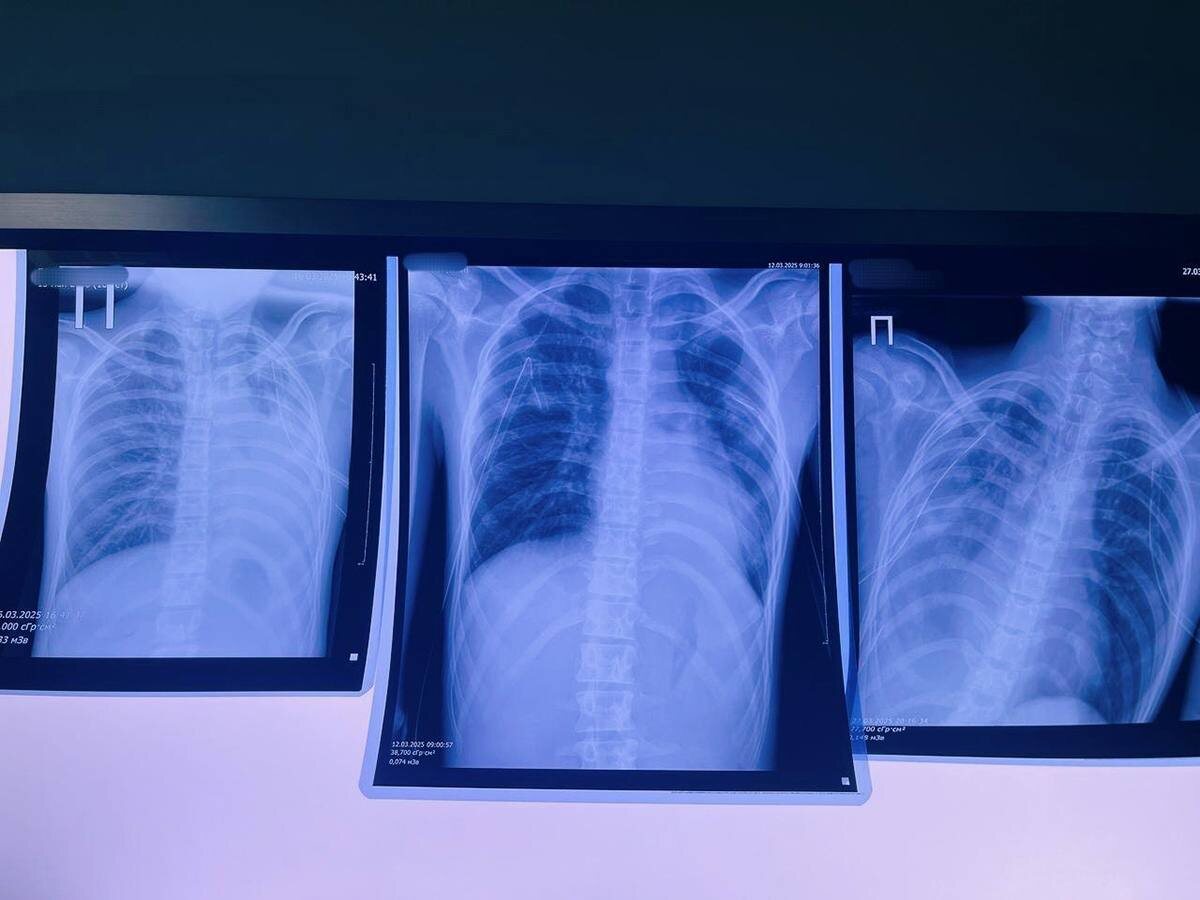

✔ История 16-летнего кировского подростка может стать уроком для молодых людей, попавших под влияние современной моды. Несколько лет вейпинга привели к образованию булл в легких, которые внезапно разорвались, вызвав двусторонний пневмоторакс. Это потребовало экстренного вмешательства и перевода пациента в Федеральную клинику, где за жизнь ребенка продолжают бороться. Это не единичный случай.

– Среди заболеваний появилось новое название «EVALI» – тяжелое поражение легких из-за токсичных веществ в жидкостях для вейпа, оно приводит буллезной болезни – образованию «пузырей» в легких, которые могут разорваться в любой момент. Особую опасность представляет ацетат витамина Е, при нагревании он превращается в клейкую массу, оседающую в легких. Случай в нашей клинике, произошедший с 16-летним подростком, – это тревожный сигнал. Когда мода оборачивается больничной койкой, стоит задуматься: нужно ли это «безопасное развлечение»? – задается вопросом заведующий хирургическим отделением детской областной больницы Виталий Лапшин.

❌ Подростки – главная мишень производителей вейпов. Яркие устройства со сладкими вкусами создают ложное впечатление безопасности. Как отмечает заведующая пульмонологическим отделением Анна Удалова, за последнее время сразу несколько детей, курящих вейпы, были госпитализированы в медучреждение.

– Сейчас в нашем отделении проходит лечение 16-летняя девушка, которая 4 года курит сигареты и 3 года – вейпы. С осени прошлого года у пациентки был кашель, который купировался на некоторое время, но потом возвращался снова. Весной 2025 года девушка обратилась с жалобами на длительный кашель и гнойную мокроту зеленого цвета. В начале апреля при проведении компьютерной томографии была установлена картина двусторонней полисегментарной бронхопневмонии и предположительная стадия проявления бронхиолита с обструкцией бронхов. Данные изменения в легких связаны с достаточно большим стажем курения, в том числе и вейпов, – подчеркнула Анна Удалова.